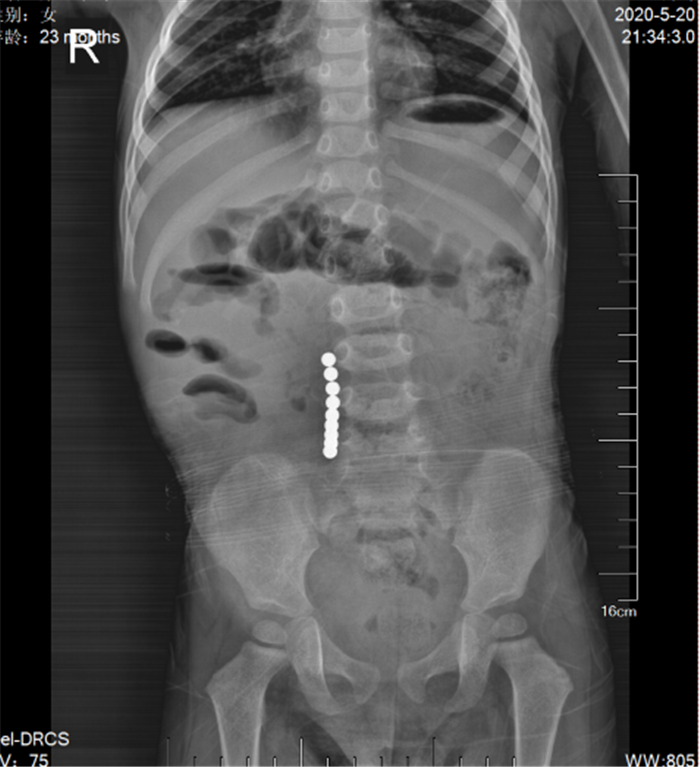

(图2)“串珠样高密度金属”影像

陈博士查体发现患儿精神差,嗜睡,脱水貌,欠配合,腹部较膨隆,全腹轻度压痛,无反跳痛、肌紧张,叩鼓音,上腹部尤甚,肠鸣音1次/分,陈博士考虑患儿有典型的“痛、吐、胀、闭”症状,“肠梗阻”可能性大,立即安排患儿做腹部卧位平片检查,发现患儿右下腹有“串珠样高密度金属”影像(图2),再追问患儿病史,急糊涂的父母才想起患儿3天前大便曾排出1粒玩具“磁力珠”(图3),当时未在意。